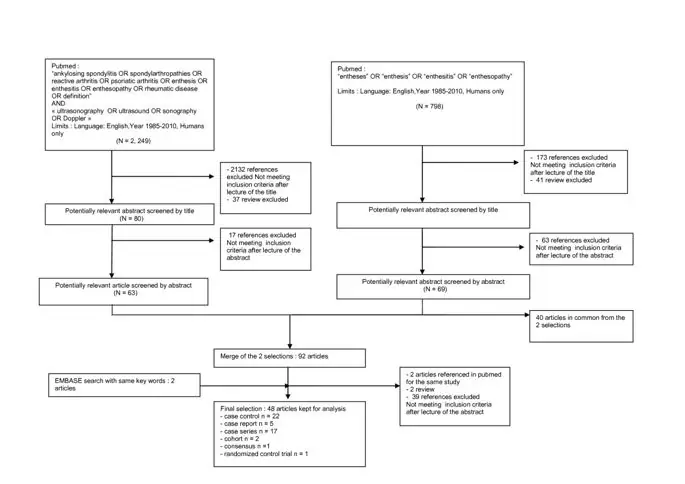

Рисунок 1 иллюстрирует блок-схему выбора статей. Из 3852 ссылок, полученных из баз данных, 237 рефератов были отобраны после прочтения названий, 94 статьи были отобраны после прочтения рефератов и, наконец, 48 статей были проанализированы для определения определения и характеристик ультразвукового энтезита. Эти статьи включали 22 исследования «случай-контроль», 5 исследований «случай-отчет», 17 исследований серии случаев, 2 когорты, 1 экспертный консенсус и 1 рандомизированное контрольное исследование (Таблица 1). Большинство из них (n = 37) были направлены на воспалительные патологии: спондилоартропатию или анкилозирующий спондилит (n = 24), спондилоартропатию или другой воспалительный ревматизм (n = 3) и псориатический артрит (n = 10). Только шесть исследований были посвящены дегенеративному вовлечению энтезы. Два исследования не сообщили диагнозы пациентов.

Блок-схема выбора статей.

Изображение в полном размере